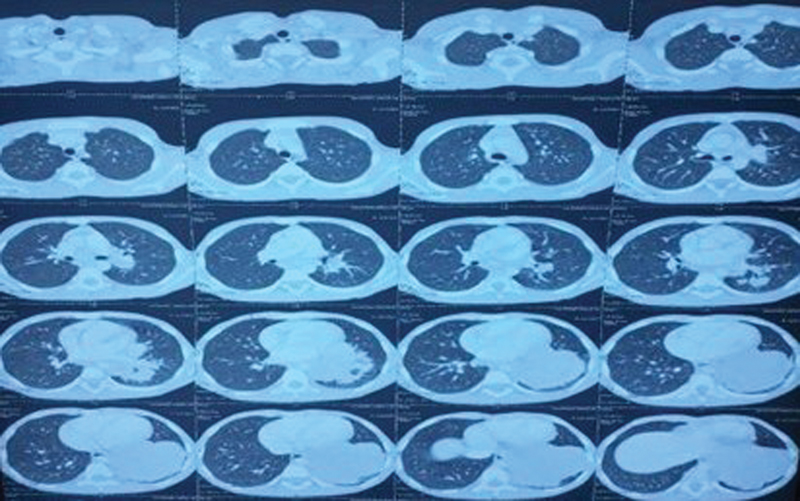

The positron emission tomography (PET) scan for staging revealed the presence of an irregularly shaped, metabolically active soft tissue mass in the lower left lung lobe. This finding suggests the possibility of primary neoplastic disease ([Fig. 2]). The mediastinal and left retrocrural regions showed small, inactive lymph nodes, indicating the presence of nearby metastatic lymph nodes. No other abnormal metabolically active lesions were found in the body. A biopsy of the lung mass found a malignant small round cell tumor, suggesting a possible diagnosis of neuroendocrine small-cell carcinoma. Microscopically, the tumor cells were arranged in sheets and occasionally displayed rosette formation. These small, round-to-oval cells exhibited a blue appearance, minimal cytoplasm, inconspicuous nucleoli, and slight overlap with nuclear molding. The stroma was thin and delicate, with occasional mitosis and patchy calcification. Immunohistochemistry (IHC) of the biopsy revealed thyroid transcription factor-1 (TTF-1) and synaptophysin positivity, while CK7 and chromogranin showed focal positivity. The biomarkers CD56, desmin, CD99, vimentin, and NKX 2.2 were found to be negative ([Fig. 3]). Fluorescence in situ hybridization (FISH) analysis revealed no evidence of EWSR1 gene rearrangement in 100% of the cells studied. Next-generation sequencing did not reveal any clinically relevant pathogenic mutations or fusions.

| Figure 2: Positron emission tomography computed tomography scan showing soft tissue mass in the lower left lung lobe.